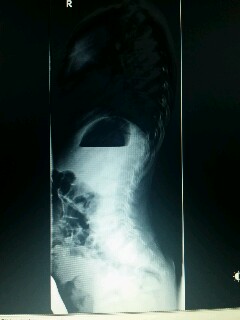

Was ich aber sehe (auf dem zweiten Bild) scheint mir ein starkes Hohlkreuz zu sein. Wenn ich das richtig interpretiere.

wie auch Thomas sehe ich keine ausgeprägte Skoliose auf dem Röntgenbild. Mir sieht irgendwie die gesamte Wirbelsäule schräg aus (evl. Folge der Beinlängendifferenz), der obere Teil des Röntgenbildes ist schlecht zu sehen. Auf dem zweiten Bild sieht es mir auch nach einem starken Hohlkreuz aus.

Und natürlich die sehr starke Lendenlordose ("Hohlkreuz").

das Hohlkreuz deiner Tochter wirkt schon sehr extrem. Ich denke, dass das Problem eher darin liegt mit einer evtl. begleitenden leichten Skoliose. Eine gewisse Asymmetrie der Taillendreiecke liegt vor, die auf eine Skoliose eher im Lendenbereich schließen lässt. Abgeklärt werden sollte das auf jeden Fall und auch entsprechend behandelt werden. Deine Tochter befindet sich noch im Wachstum, da kann sich vieles schnell verändern. Aber bei Dr. Hoffmann seid ihr in guten Händen, auch wenn es noch ein Weilchen hin ist bis zum Termin.